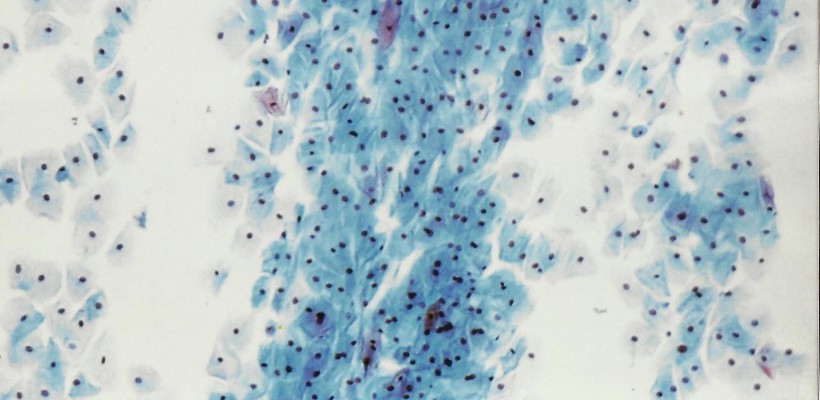

Cytologie G.S.C.C. prise d’une greffe mince

On voit surtout les keratinocytes à differents étapes de leur évolution.